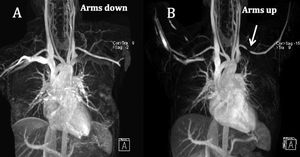

Thoracic Outlet Syndrome (TOS) refers to the constellation of symptoms due to compression of the brachial plexus and subclavian vessels as they traverse the thoracic outlet between the anterior and middle scalene muscles. MRA is the preferred imaging modality for TOS because of its better soft tissue resolution and tissue characterization capability without the use of radiation. Upper extremity abduction is the standard practice and is shown to be effective as a positional maneuver for diagnosis of TOS. Diameter change by 430% for subclavian artery and by 450% for subclavian vein between the neutral and abducted extremity positions is considered significant for the diagnosis of TOS (fig.) Figure Coronal MIP MRA image with arms down (A) shows normal upper extremity inflow arteries. Coronal MIP MRA with abduction of the arms (B) shows severe stenosis of the left subclavian artery (arrow) suggesting arterial thoracic outlet syndrome (P. Nagpal et al. 2016)